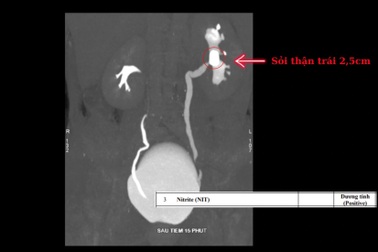

Chữa đau lưng 6 năm mới phát hiện nguyên nhân do sỏi thận6 năm sống chung với cơn đau lưng dai dẳng dù đã điều trị đủ cách bằng cả Đông và Tây y, bà T.T.H (62 tuổi) không ngờ nguyên nhân do viên sỏi thận lớn âm thầm tổn thương cho thận và chỉ được phát hiện khi bà nhập viện cấp cứu.